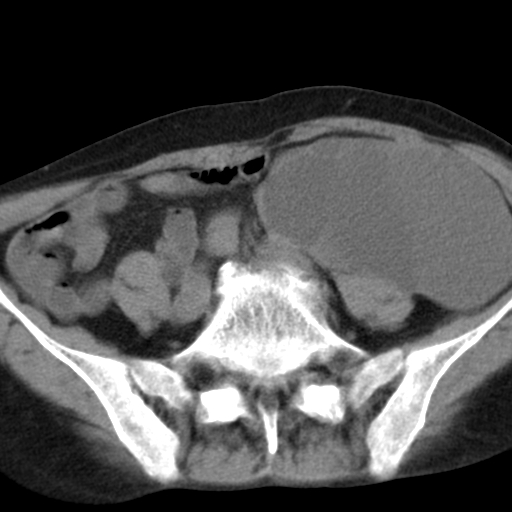

女,70,腹部间断性胀痛三月余

子宫宫腔及双侧附件积液,原因?

考虑卵巢囊腺瘤,不排除囊腺癌。

考虑卵巢囊腺瘤或囊腺癌。实质成分太多,考虑后者可能性大.

年龄较大还是恶性可能大,不排除库肯勃瘤

双侧卵巢粘液性囊腺癌,不多赘述。

考虑卵巢囊腺瘤;囊腺癌不能排除(理由:病人年龄较大,病灶外形欠规整、囊实相间,实性成分较多均支持囊腺癌)。要是能听听九目段老师的点评就好了!

年龄较大,囊实相间,实性成分较多均支持囊腺癌。

考虑囊腺癌,子宫病变不能排除吧,建议mri检查。